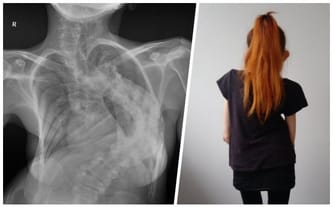

The last call for help! Scoliosis kills, Patrycja is in danger!

Fundraiser goal: Urgent surgery to stabilize and resect the spine in the Czech Republic

Skrzywienie udało się zmniejszyć do około 75 stopni. To nadal dużo i niewykluczone, że jeszcze będę potrzebowała kiedyś ponownej operacji. W tym momencie jednak jest nieźle, a co najważniejsze moje serce i płuca chociaż trochę odetchnęły.